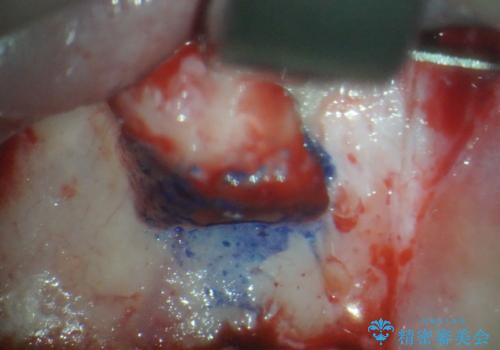

両歯とも根尖部付近を歯肉から触れると痛みを感じており、3次元CTを撮影したところ、前から2番目の歯の根尖部に病変があることが分かりました。

以前歯根端切除術を受けているものの、現在の主流とは異なる術式で行われているため、再度歯根端切除術を行うこととしました。